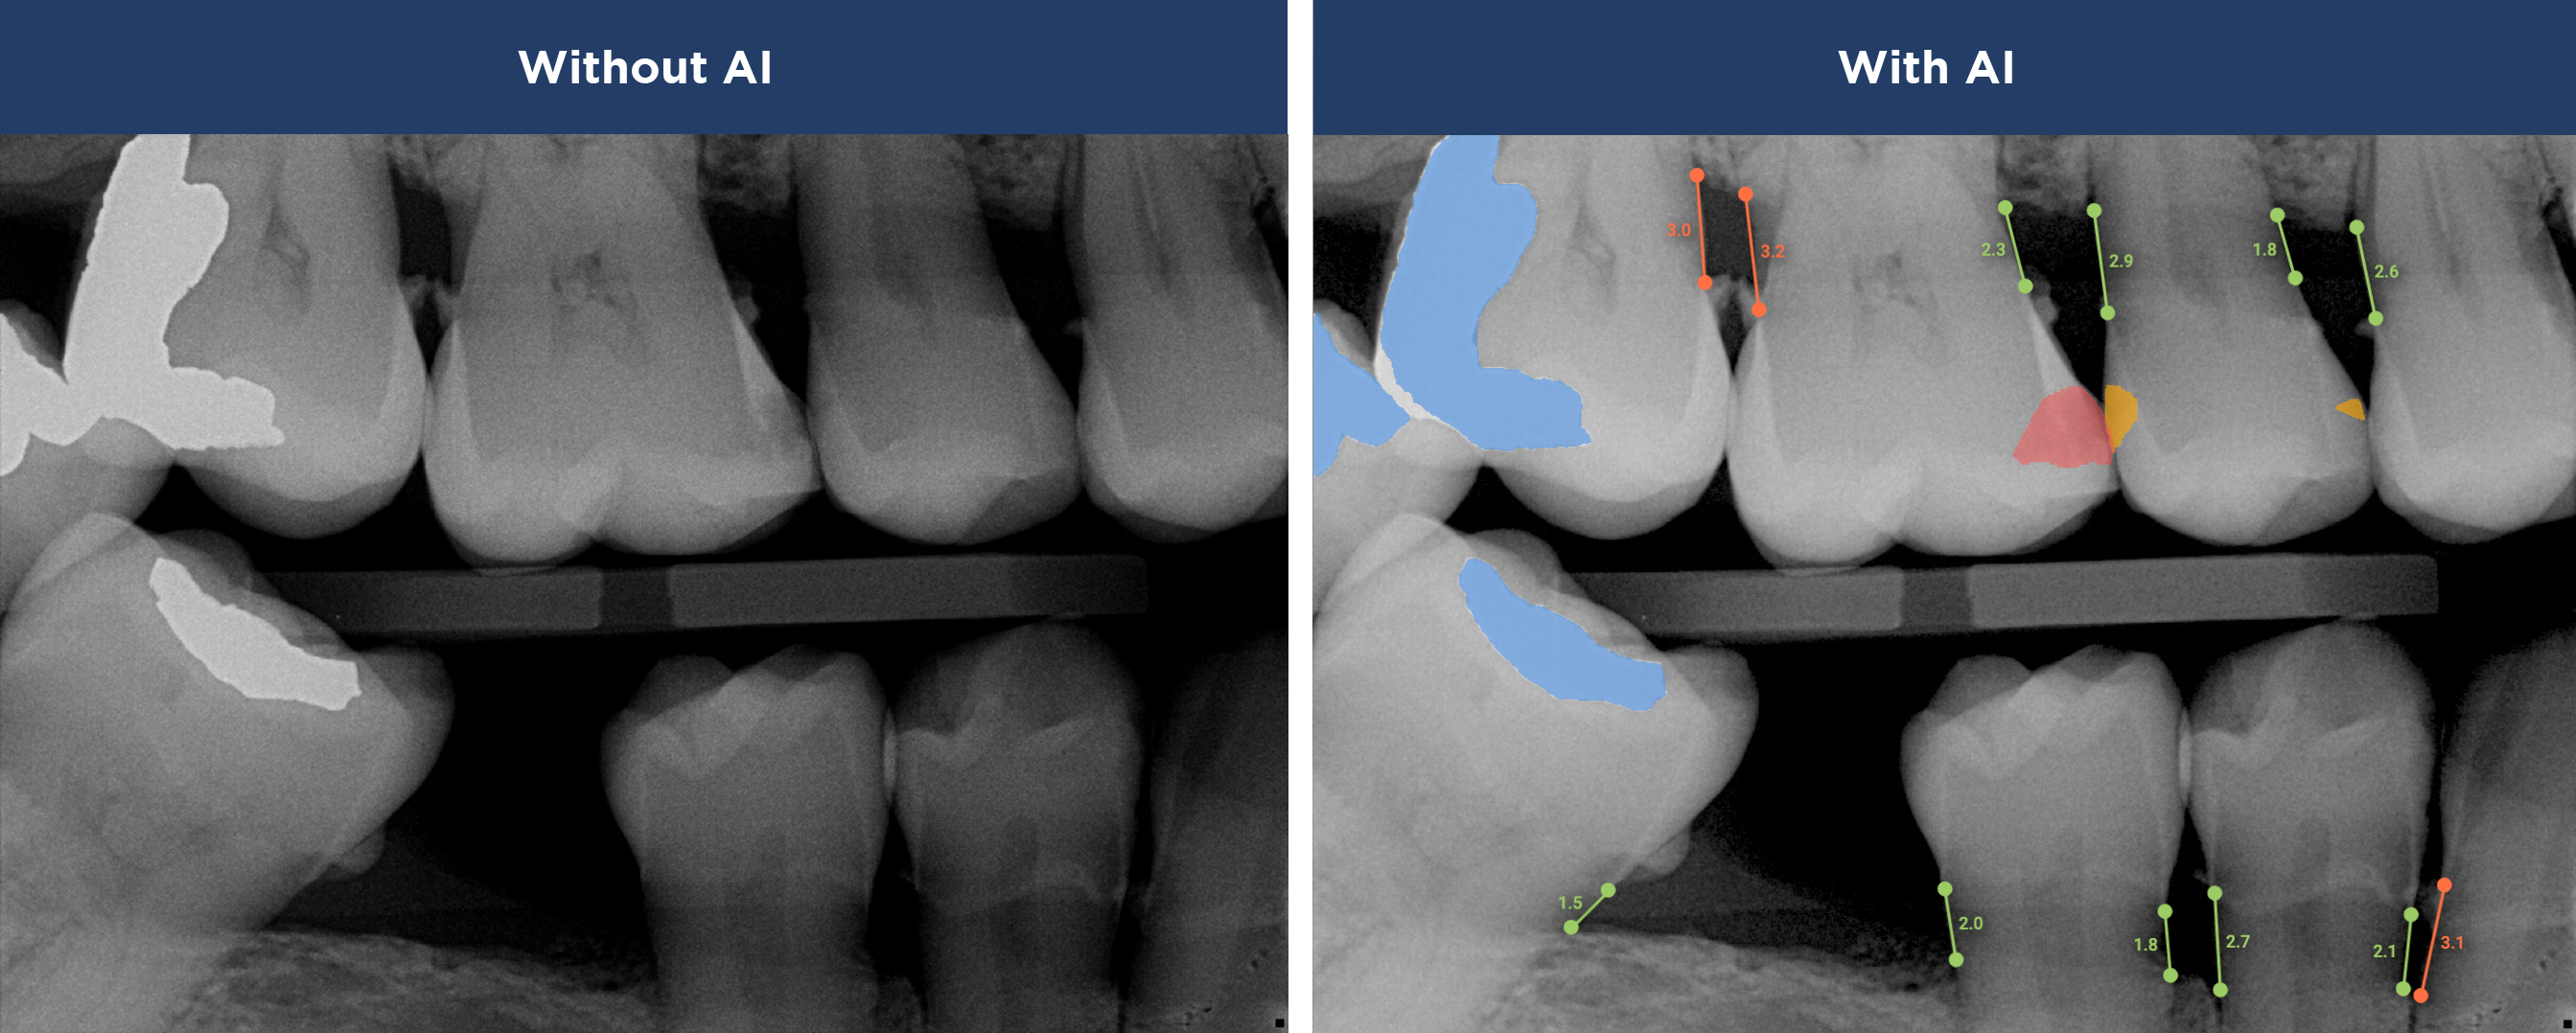

Overjet’s artificial intelligence technology transforms traditional black-and-white X-rays by adding a layer of data that instantly outlines decay (cavities) and measures bone loss. This makes it easy for you to see your results alongside your dentist.  It’s like getting a second opinion delivered instantly. With Overjet’s analysis and easy-to-read presentation, you will have the information you need to make an informed decision about your oral health. Together, we’ll review your findings and discuss the best steps to take to achieve your goals.